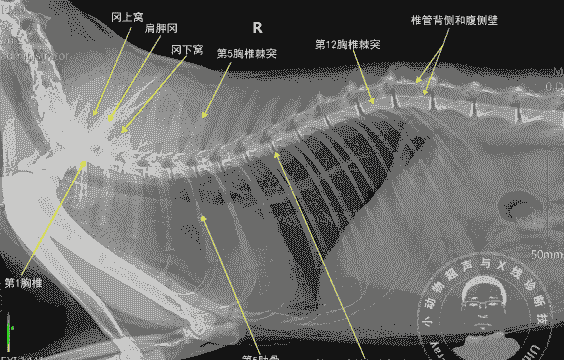

脊髓损伤通常是由于脊柱骨折或脱位引起的。猫的常见病因包括车祸、咬伤和枪伤。这种损伤不仅会对脊髓造成初始损伤,还会导致肿胀、出血、神经鞘破坏和组织腐烂等继发性损伤。脊柱创伤的症状通常突然发作,并可能逐渐恶化。中背部或下背部的严重脊髓损伤可能会导致僵硬瘫痪,或跛行瘫痪,在几天内蔓延到全身,导致呼吸麻痹死亡。x光片上可能会看到椎骨骨折或脱位,但可能需要计算机断层扫描才能看到一些骨折。如果在受伤后的最初几个小时内开始药物治疗,可能会有所帮助。有轻度神经系统损伤症状的动物通常在笼内休息4至6周后恢复。对于导致严重神经系统症状的某些类型的损伤,手术是必要的。在脊髓损伤下方失去疼痛感觉能力的猫中,康复前景很差。